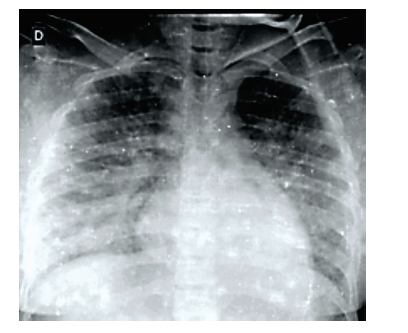

Uma paciente de doze anos de idade, proveniente do Quênia há vinte dias, foi internada com quadro de febre diária há quinze dias, mal-estar, icterícia, dor abdominal intensa, falta de ar e hematúria macroscópica. Ao exame físico, apresentava-se em mau estado geral, ictérica ++/4+, descorada +++/4+, com palidez acentuada, ortopneica, edemaciada, com FR de 30 irpm, FC de 160 bpm, temperatura de 39 ºC, PA de 80 x 50 mmHg e saturação periférica de O2 de 90% em ar ambiente. Ausculta Pulmonar: murmúrio vesicular presente e diminuído bilateralmente, com alguns estertores crepitantes finos em ambas as bases. Ausculta Cardíaca: bulhas rítmicas normofonéticas e taquicárdicas e segunda bulha desdobrada, sem sopros. Abdome tenso, depressível, com resistência voluntária à palpação, fígado endurecido e doloroso, palpável a 6 cm do rebordo costal direito, baço a 4 cm do rebordo costal esquerdo. Edema de membros inferiores ++/4+. Tempo de enchimento capilar de 3 s. Durante a análise do hemograma, foram encontrados P. falciparum (mais de 5.000 parasitas/μL de sangue). Realizou, ainda, o raio-X de tórax mostrado abaixo.

Considerando esse caso hipotético, assinale a alternativa correta.